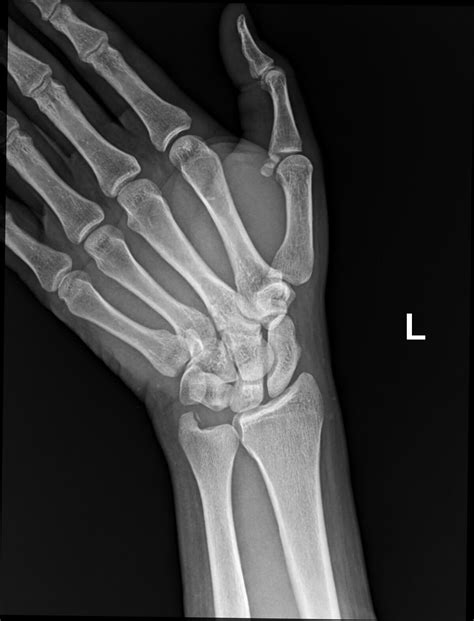

Fractures of the Styloid Process Ulna are relatively rare but can occur due to trauma, such as a fall on an outstretched hand or a direct blow to the wrist. These fractures can be challenging to diagnose due to their small size and the overlap of other bony structures on radiographs. However, they can cause significant pain and instability in the wrist joint.

Imaging studies, such as X-rays, CT scans, and MRI, can provide detailed information about the Styloid Process Ulna and surrounding structures. These studies can help identify fractures, degenerative changes, and other abnormalities.

Diagnosing conditions related to the Styloid Process Ulna typically involves a combination of clinical examination, imaging studies, and, in some cases, arthroscopy. Treatment options vary depending on the severity and underlying cause of the condition.